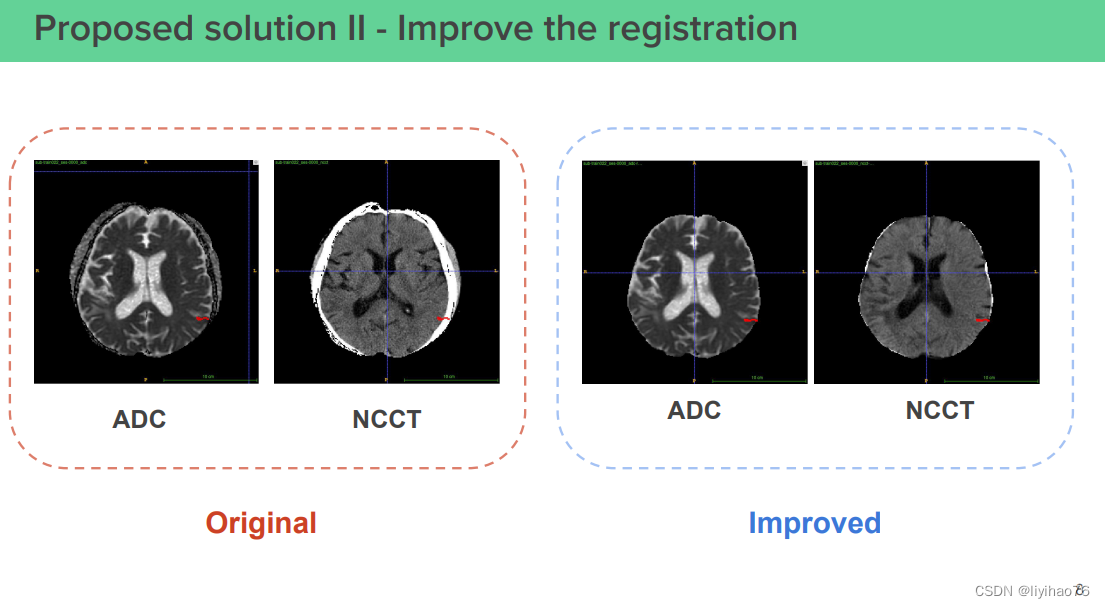

(0) 优化配准